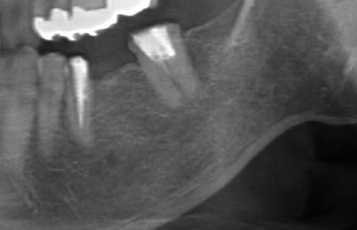

臼歯大きくGBR(骨造成)50代男性

治療前

治療後

施術名 | 抜歯GBR(骨造成)そーせじテクニック →インプラント埋入 |

---|---|

主訴 | 噛めない |

施術の副作用(リスク) | 脱落感染 |

施術の価格 | 1本GBR5万~10万(税抜き)+インプラント埋入補綴まで35万(税抜き) FGG5万 ソケットリフト6万 |

コメント | 臼歯部はほとんど骨がなく垂直的に骨を作ってからインプラント埋入を行いました |